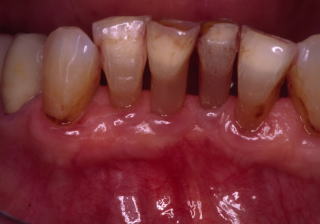

(図1)初診時(1975年10月15日)、38歳。歯肉出血が主訴で紹介された。当時、歯周疾患治治療は一部の臨床家以外はあまり関心が払われていなかった

(図2)初診時(1975年10月15日)、38歳。まず徹底的なPlaque Controlから始めた

★歯周病の治療とは、20年30年と抜かずに、口腔内が健康でQOLを維持できることである★

★生活習慣病のため短期間で治癒する病気ではない★